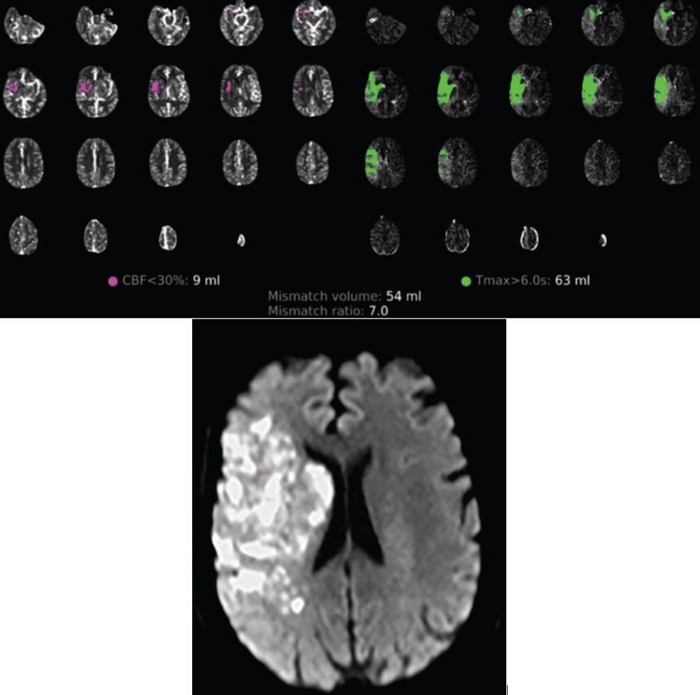

Leesburg, VA, May 18, 2023 According to an accepted manuscript published in ARRS’ own American Journal of Roentgenology ( AJR ) , SARS-CoV-2 infection may promote continued infarction progression, despite angiographic reperfusion, in vaccine-naïve patients with large-vessel occlusion acute ischemic stroke (AIS).

This AJR accepted manuscript compared 100 consecutively presenting patients with COVID-19 and AIS between March 2020 and April 2021 with a contemporaneous cohort of 282 patients with AIS who did not have COVID-19. Reperfusion classes were dichotomized into positive (extended thrombolysis in cerebral ischemia [eTICI] score = 2c–3) and negative (eTICI score < 2c) groups. All patients underwent endovascular therapy following initial CT perfusion imaging (CTP) to document infarction core and total hypoperfusion volumes.

Ultimately, in this case-control study of vaccine-naïve patients with and without COVID-19 with infarct growth after endovascular reperfusion during acute ischemic stroke, COVID-19 was a significant predictor for absolute infarct growth of 15 cm3 or more (OR, 5.1 [95% CI, 1.0–25.95]; p = .05).

“These findings support the potentially aggressive clinical course of cerebrovascular events in patients with COVID-19, suggesting greater infarction growth and ongoing consumption of at-risk tissues, even following angiographic reperfusion,” Dehkharghani et al. added.